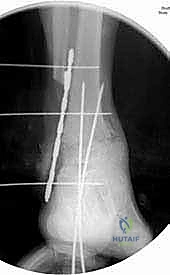

- Finally, use the guide pins to place a 6.5or 7.3-mm cannulated cancellous screw from the posterior tibia into the head of the talus to increase rigid fixation and further control rotation and from the anterior tibia into the tuberosity of the calcaneus ( TECH FIG 6 ).

Calcaneus A TECH FIG 6

- A. Blade plate and screw fixation construct for tibiocalcaneal arthrodesis. (continued)

TECH FIG 6 • (continued) B–D. Postoperative radiographs of tibiocalcaneal arthrodesis. B. Lateral view. C. AP view. D. Mortise view. E, F. Sawbones model with blade plate in optimal position.